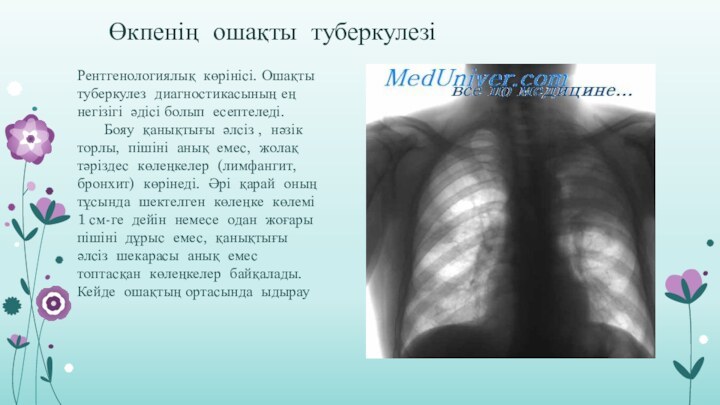

Симптомы и признаки туберкулеза: как распознать заболевание

Раздел: Визуальные уроки